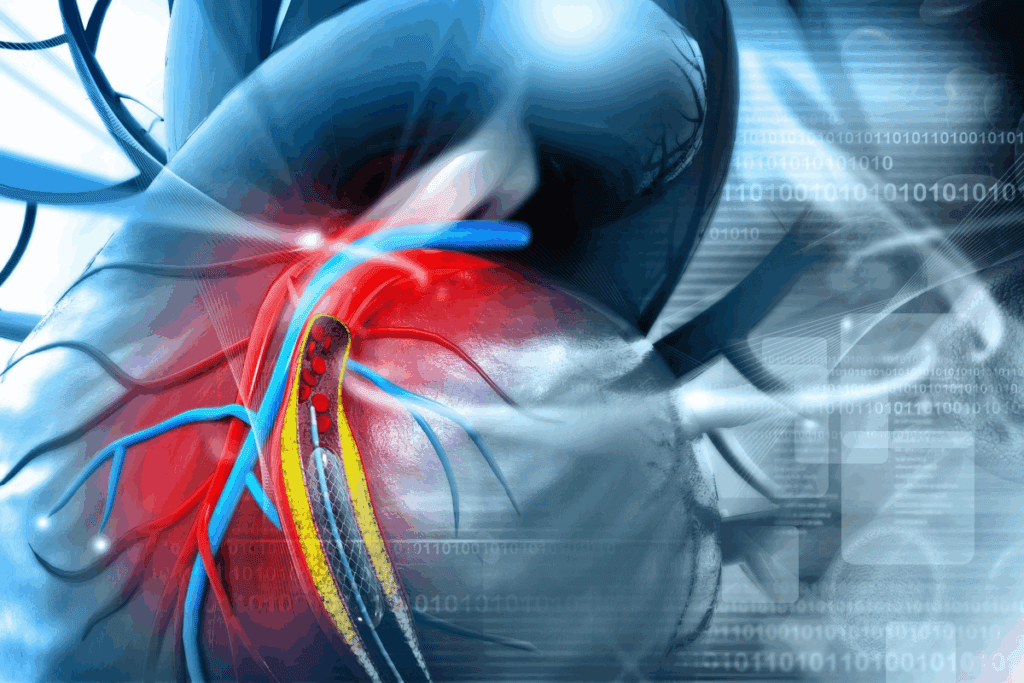

Medical imaging has improved, letting us see coronary arteries in great detail. Coronary artery photos from angiography and other methods give us important insights into the heart’s blood flow.

Today’s imaging, like coronary angiography, cardiac CT, and MRI, helps us see the arteries and spot problems. These images are key for making treatment choices, like angioplasty or bypass surgery.

By mixing coronary artery photos with patient data, doctors can create treatment plans that meet each person’s needs.

Interventional methods like angioplasty and stenting open blocked arteries. Surgery, like CABG, might be needed for severe or complex blockages. The choice between these options depends on the blockage’s location, severity, and the patient’s health.